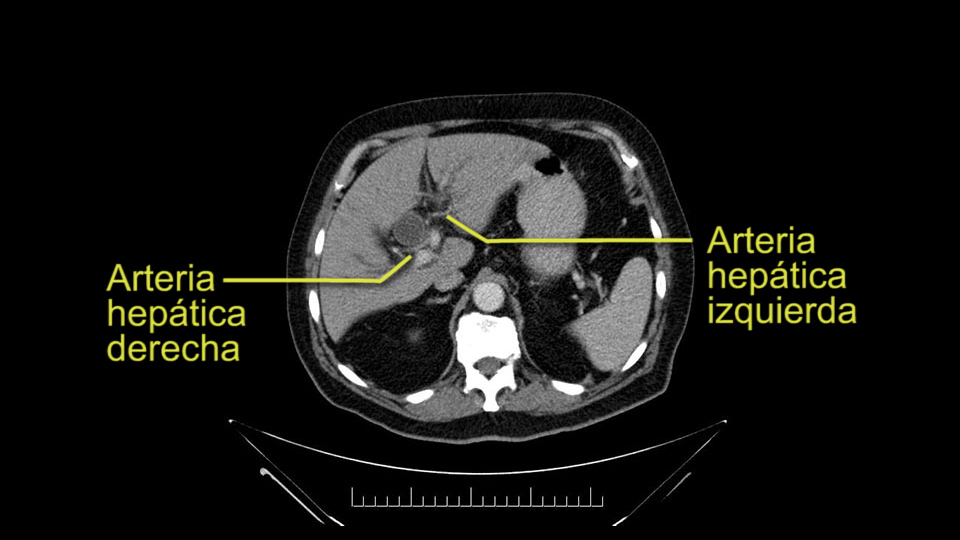

He has normal arterial anatomy: no accessory or replaced right hepatic artery, which is important because sometimes the right hepatic artery can come behind the neck of the pancreas and you have to be careful of that in a Whipple dissection.

Then you look for anomalies. The one you worry about the most doing a Whipple is a replaced or aberrant right hepatic artery coming off the SMA at its origin. So again, find the SMA. You can find it because the renal vein goes through it. Follow it up, up-up-up. Nothing coming off of there that I can see here. Nothing coming off of it, nothing coming off of it and just to confirm it, look at the celiac trfurcation. There’s the celiac, there’s the bifurcation, there's the splenic artery, hepatic artery. Make sure there’s a right, which there is here. The right usually goes under the bile duct: important when you’re going around the bile duct to do a Whipple. A replaced right goes under the portal vein and the bile duct way over here on the right. That’s about it.

The other slowing down moment would be the gastroduodenal artery. Confirming that the gastroduodenal artery is not a dominant artery supplying blood to the liver. Liver failure is something which we don’t want due to altered blood supply to the liver or hampered arterial blood supply to the liver. So I would dissect out the hepatic artery, the left and right branches very clearly. Put a bulldog clamp on the gastroduodenal artery, make sure that the perfusion of the liver is excellent on the right and left side, and then divide the gastroduodenal artery. I would avoid using crushing instruments or crushing clamps on the gastroduodenal artery because they have a tendency to shatter in patients who are old with friable vessels so you have to be careful and tackle it with the help of a 5-0 or a 6-0 prolene sutures. In younger patients, I would just apply clips and move on when it comes to dividing the gastroduodenal artery.

To plan a pancreatoduodenectomy, we start by reviewing the vascular anatomy, especially the origin of the celiac trunk, here, in front of the aorta, looking for any evidence of stenosis. In addition, we look at the origin of the superior mesenteric artery, to look for any branches, and any replaced right hepatic arteries coming from the superior mesenteric artery; which does occur in about 12% of the population.

The second point about the vascular anatomy-, is to again look for right hepatic arteries in the hilum, coming from the superior mesenteric artery by palpating-through the Winslow Hiatus. Usually we will check for a pulse in the posterior aspect of the hepatic hilum, where a right hepatic artery should not usually be found. In this case, the precaution is to avoid an accidental ligation of the right hepatic artery that might jeopardize perfusion of the right lobe, or if there is a completely replaced hepatic artery that can put the liver circulation at risk.

E l segundo punto de la anatomía vascular, es nuevamente buscar arterias hepáticas derechas, en el hilio, provenientes de la mesentérica superior y eso lo hacemos palpando -a través del Hiato de Winslow- el hilio hepático y usualmente sentiremos un pulso en el aspecto posterior del hilio hepático, donde no debe ir el recorrido usual de la rama derecha de la arteria hepática. En este caso, la precaución es no realizar una ligadura accidental de la arteria hepática derecha y poner en riesgo -posiblemente- la perfusión del lóbulo derecho, o aún esta arteria puede reemplazar completamente la arteria hepática y poner en riesgo la circulación del hígado.

I am a believer in pylorus preservation. And in this case I see no reason why that wouldn't be possible. Mobilize the duodenum, divide the gastroepiploic vessels and divide the duodenum. I try to divide it with a linear stapler about four centimeters from the pylorus to have adequate length for my GI anastomosis. This facilitates exposure of the head neck of the pancreas. I find the gastroduodenal artery. This patient has normal arterial anatomy. Always on every preoperative CT scan I look to see if there is a replaced right hepatic. In this case I did not see one. Regardless of how confident I am I always look carefully for variant anatomy. I always do a clamp test on the GDA before ligation. I doubly ligate the GDA with not just a tie but a suture ligature because of the risk of GDA blowout in patients with a leak.